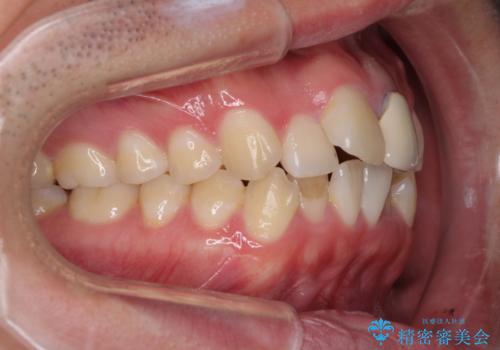

前歯の歯並びとクラウンを改善 インビザラインとオールセラミック

- 前歯の歯並びと不自然な色をした前歯のクラウンを気にして来院された患者様です。

上下前歯の歯列不正はインビザラインにより歯列を整え、その後に、前歯をオーダーメイドタイプのオールセラミッククラウンにて補綴治療することとしました。

初診時には、歯並びを整えることのみを検討されていましたが、歯列が整うにつれて不自然な色合いが気になるようになり、矯正治療を行ってから補綴治療をする計画を受け入れてくださいました。

口元の印象が明るく変わり、患者様には大変満足していただきました。